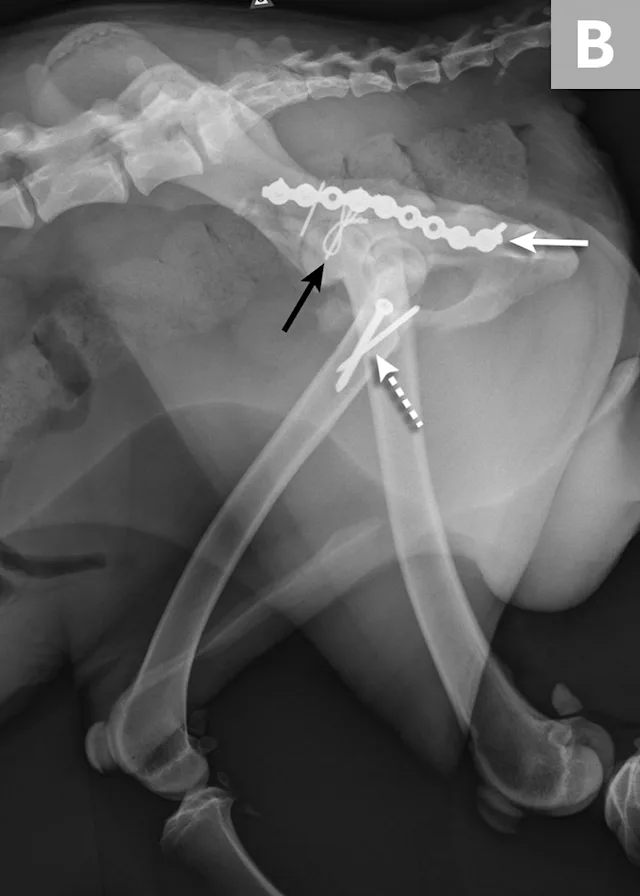

FIGURE 1A

An 11-year-old intact female Welsh corgi with injuries of the weight-bearing axis of the pelvis. Ventrodorsal (A) and lateral (B) projection images show a left sacroiliac luxation with cranial and ventral displacement (black arrow). Pubic fracture with lateral displacement (dashed arrow) and an oblique tibial fracture (white arrows) were additional comorbidities. The tibial fracture was treated surgically with an internal plate fixation, and the pelvic injuries were managed conservatively.